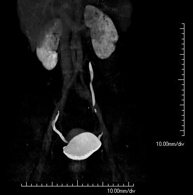

- Angio-TC aorta abdominal  Prueba diagnóstica no invasiva que consiste en el estudio de la arteria aorta abdominal obteniendo imágenes de alta definición anatómica mediante el empleo de un equipo de TC (Tomografía Computarizada) y de contraste yodado. La calidad de las imágenes permite realizar reconstrucciones en 2D y 3D gracias a estaciones de trabajo especializadas en el estudio arterial. Está indicado en aquellos pacientes con enfermedad vascular (aterosclerosis), en aneurismas de aorta, en pacientes con dolor abdominal de posible origen vascular, en estudios pre-quirúrgicos de lesiones adyacentes a la aorta abdominal como "mapa" vascular, etc. La información obtenida de forma no invasiva es indispensable para los pacientes que requieren tratamiento percutáneo o quirúrgico. En aquellos pacientes que solo requieren un seguimiento de las lesiones vasculares, esta técnica es la técnica no invasiva de elección junto con la angio-RM. Prueba diagnóstica no invasiva que consiste en el estudio de la arteria aorta abdominal obteniendo imágenes de alta definición anatómica mediante el empleo de un equipo de TC (Tomografía Computarizada) y de contraste yodado. La calidad de las imágenes permite realizar reconstrucciones en 2D y 3D gracias a estaciones de trabajo especializadas en el estudio arterial. Está indicado en aquellos pacientes con enfermedad vascular (aterosclerosis), en aneurismas de aorta, en pacientes con dolor abdominal de posible origen vascular, en estudios pre-quirúrgicos de lesiones adyacentes a la aorta abdominal como "mapa" vascular, etc. La información obtenida de forma no invasiva es indispensable para los pacientes que requieren tratamiento percutáneo o quirúrgico. En aquellos pacientes que solo requieren un seguimiento de las lesiones vasculares, esta técnica es la técnica no invasiva de elección junto con la angio-RM.

- Angio-TC aorto-ilíaco Prueba diagnóstica no invasiva que consiste en el estudio de las arterias ilíacas y la aorta abdominal obteniendo imágenes de alta definición anatómica mediante el empleo de un equipo de TC (Tomografía Computarizada) y de contraste yodado. La calidad de las imágenes permite realizar reconstrucciones en 2D y 3D gracias a estaciones de trabajo especializadas en el estudio arterial. Esta prueba está especialmente indicada como estudio pre-quirúrgico (mapa vascular) antes de intervenciones percutáneas o quirúrgicas de aorta abdominal, como el estudio complementario en pacientes con isquemia de miembros inferiores, etc. Prueba diagnóstica no invasiva que consiste en el estudio de las arterias ilíacas y la aorta abdominal obteniendo imágenes de alta definición anatómica mediante el empleo de un equipo de TC (Tomografía Computarizada) y de contraste yodado. La calidad de las imágenes permite realizar reconstrucciones en 2D y 3D gracias a estaciones de trabajo especializadas en el estudio arterial. Esta prueba está especialmente indicada como estudio pre-quirúrgico (mapa vascular) antes de intervenciones percutáneas o quirúrgicas de aorta abdominal, como el estudio complementario en pacientes con isquemia de miembros inferiores, etc.

- Angio TC d'aorta abdominal Prova diagnòstica no invasiva que consisteix en l'estudi de l'artèria aorta abdominal amb l'obtenció d'imatges d'alta definició anatòmica mitjançant l'ús d'un equip de TC (Tomografia Computaritzada) i contrast iodat. La qualitat de les imatges permet realitzar reconstruccions en 2D i 3D gràcies a estacions de treball especialitzades en l'estudi arterial. Està indicat en aquells pacients que pateixen malaltia vascular (arteriosclerosi), aneurismes d'aorta, en pacient amb dolor abdominal d'un possible origen vascular, en estudis prequirúrgics de lesions adjacents a l'aorta abdominal com el "mapa" vascular, etc. La informació obtinguda de forma no invasiva és indispensable per als pacients que requereixen tractament percutani o quirúrgic. En aquells pacients que només requereixen un seguiment de les lesions vasculars, aquesta tècnica és la tècnica no invasiva d'elecció juntament amb l'angio RM. Prova diagnòstica no invasiva que consisteix en l'estudi de l'artèria aorta abdominal amb l'obtenció d'imatges d'alta definició anatòmica mitjançant l'ús d'un equip de TC (Tomografia Computaritzada) i contrast iodat. La qualitat de les imatges permet realitzar reconstruccions en 2D i 3D gràcies a estacions de treball especialitzades en l'estudi arterial. Està indicat en aquells pacients que pateixen malaltia vascular (arteriosclerosi), aneurismes d'aorta, en pacient amb dolor abdominal d'un possible origen vascular, en estudis prequirúrgics de lesions adjacents a l'aorta abdominal com el "mapa" vascular, etc. La informació obtinguda de forma no invasiva és indispensable per als pacients que requereixen tractament percutani o quirúrgic. En aquells pacients que només requereixen un seguiment de les lesions vasculars, aquesta tècnica és la tècnica no invasiva d'elecció juntament amb l'angio RM.

- Angio TC d'aorta-ilíaca Prova diagnòstica no invasiva que consisteix en l'estudi de les artèries ilíaques i l'aorta abdominal amb l'obtenció d'imatges d'alta definició anatòmica mitjançant l'ús d'un equip de TC (Tomografia Computaritzada) i contrast iodat. La qualitat de les imatges permet realitzar reconstruccions en 2D i 3D gràcies a estacions de treball especialitzades en l'estudi arterial. Aquesta prova està especialment indicada com a estudi prequirúrgic (mapa vascular) abans d'intervencions percutànies o quirúrgiques d'aorta abdominal, estudi complementari en pacients amb isquèmia de membres inferiors, etc. Prova diagnòstica no invasiva que consisteix en l'estudi de les artèries ilíaques i l'aorta abdominal amb l'obtenció d'imatges d'alta definició anatòmica mitjançant l'ús d'un equip de TC (Tomografia Computaritzada) i contrast iodat. La qualitat de les imatges permet realitzar reconstruccions en 2D i 3D gràcies a estacions de treball especialitzades en l'estudi arterial. Aquesta prova està especialment indicada com a estudi prequirúrgic (mapa vascular) abans d'intervencions percutànies o quirúrgiques d'aorta abdominal, estudi complementari en pacients amb isquèmia de membres inferiors, etc.